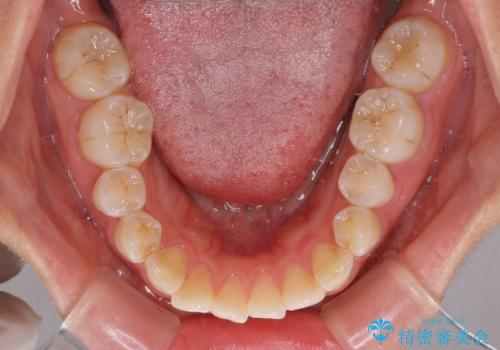

前歯の捻れを改善 インビザラインによる矯正治療

- 前歯の翼状捻転を気にして来院された患者様です。

全体的に叢生は軽度であったため、インビザラインにて矯正治療を行うこととしました。

前歯の幅の大きさも気になっていたため、IPRにより叢生を解消するとともに、歯の大きさも改善しました。